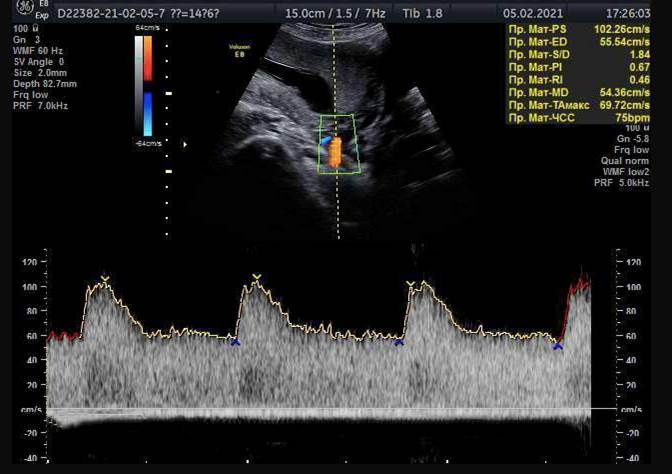

Предлагаю Вам побыть в роли эксперта ФМФ и оценить правильность получения изображения кровотока в маточных артериях для скрининга преэклампсии в 1 триместре. Для данного вопроса я взяла реальные случаи от разных докторов с сайта ФМФ.

Изображение 2

- Контрольный объем (должен быть равен 2 мм)

- Скорость (должна быть больше 60 см/сек)

- Угол инсонации (не более 30 градусов)